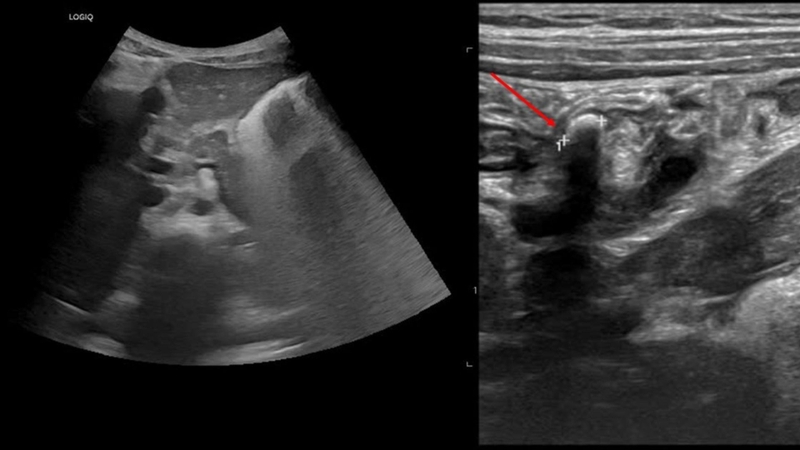

Ruột thừa bị viêm

Trên siêu âm, ruột thừa bị viêm thường xuất hiện dưới dạng một cấu trúc ống chứa dịch, có đặc điểm tương tự như ruột nhưng không thể bị đè ép, với thành dày và đường kính lớn hơn 6-7 mm. Khi sử dụng đầu dò siêu âm để ấn lên viết vùng bụng, bác sĩ có thể phân biệt giữa một quai ruột di động và một ruột thừa viêm cố định. Ngoài ra, kỹ thuật Doppler màu và Doppler năng lượng sẽ cho thấy tình trạng tăng tưới máu ở thành ruột thừa, hỗ trợ xác định mức độ viêm. Khi kết quả siêu âm viêm ruột thừa xác định tình trạng viêm ruột thừa cấp, người bệnh cần được phẫu thuật ngay mà không cần thực hiện thêm các xét nghiệm hình ảnh khác.

Viêm ruột thừa ở đỉnh

Ấn nhẹ vào hố chậu phải có thể giúp quan sát rõ hơn tình trạng viêm ruột thừa, đặc biệt khi ruột thừa nằm sau manh tràng. Nếu viêm chỉ khu trú ở phần cuối ruột thừa (viêm ruột thừa "đỉnh"), bác sĩ cần quan sát toàn bộ cấu trúc ruột thừa để đánh giá chính xác. Ngoài ra, phát hiện sỏi phân trong ruột thừa là một dấu hiệu quan trọng, hỗ trợ xác định chẩn đoán viêm ruột thừa khi có nghi ngờ trên lâm sàng.